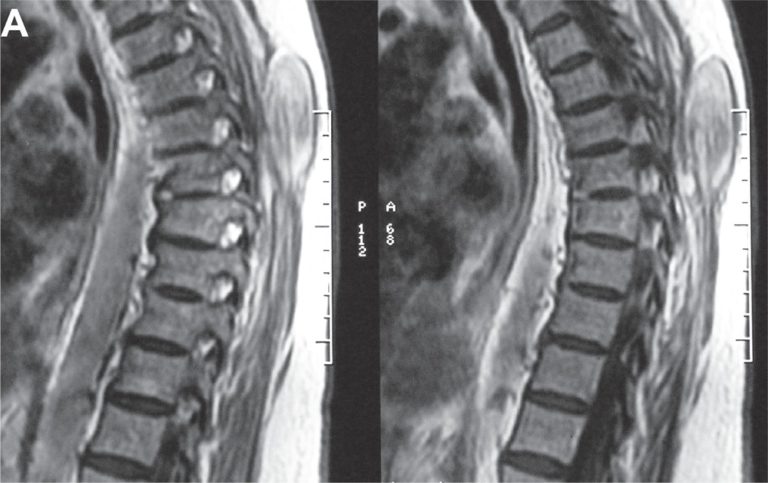

Uma senhora branca, de 84 anos, necessitou de tratamento neurocirúrgico devido a um neuroma na raiz direita de T12, após uma paraparesia progressiva. Contudo, 8 meses após a cirurgia, observou-se um edema paravertebral indolor e não pulsátil. Um exame de ressonância magnética revelou um grande tumor paravertebral hiperintenso à direita, em imagens ponderadas em T1 e T2. Uma massa paravertebral bem delimitada, não associada ao sistema nervoso central, foi identificada durante a cirurgia. Esse tumor foi removido completamente e definido como desmoide. Não havia história pessoal ou familiar de polipose. O quadro teve um bom desfecho e a paciente faleceu 3 anos depois, devido a outras complicações clínicas.